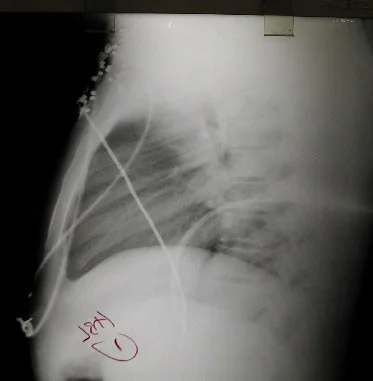

Shotgun pellets 1

Shotgun pellets 2